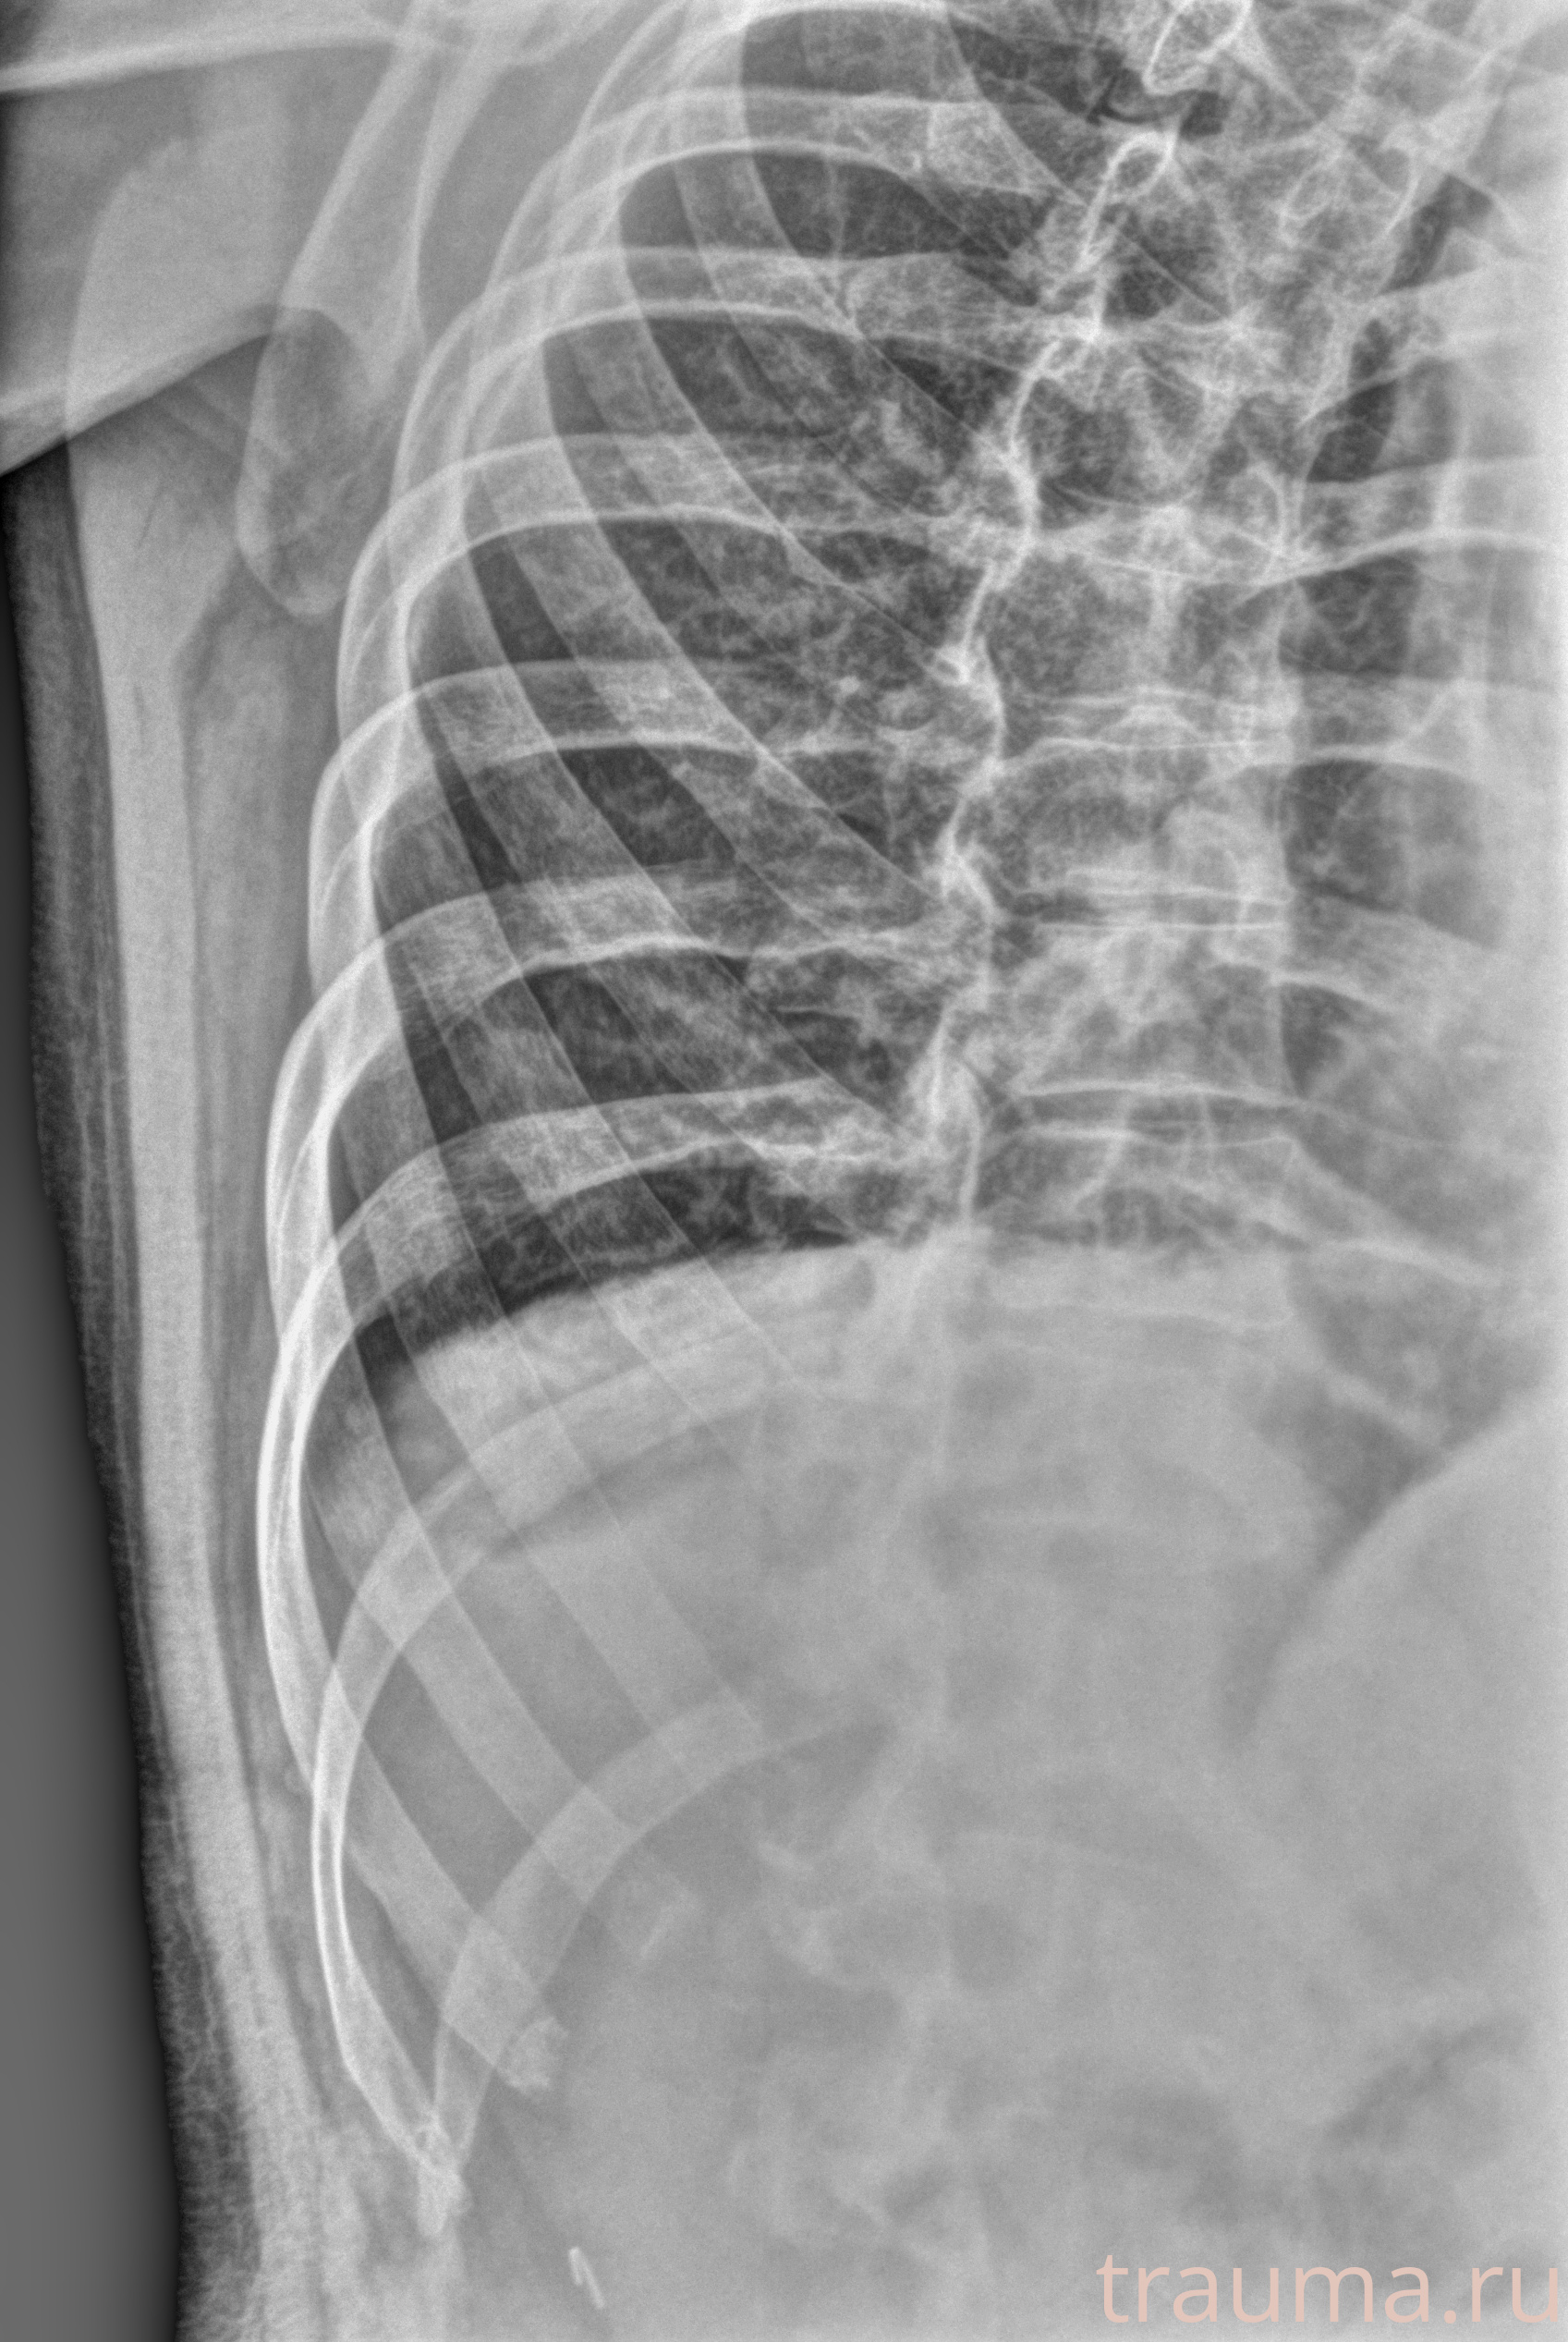

Рентген на дому: по вашему адресу приезжает врач-рентгенолог, травматолог-ортопед с мобильным рентгеновским аппаратом, проводит диагностику травмы или заболевания, делает необходимые рентгенограммы, дает рекомендации по дальнейшему лечению. Получить качественные снимки в домашних условиях возможно благодаря уникальной методике, разработанной МосРентген Центром для института  Склифосовского